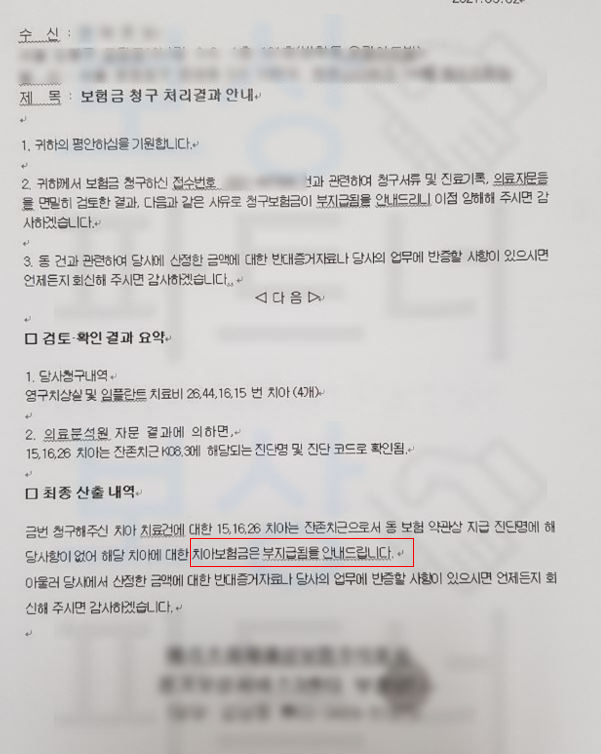

위 내용처럼 4개의 치아를 발치후 임플란트 했지만 청구서류 및 진료기록, 의료자문 결과 무려 3개의 치아가 K08.3 잔존치근에 해당하여 청구한 보험금이 부지급된다는 통보를 받고 연락주셨는데요, 이미 부지급통보를 받고 연락주셨기에 쉽지 않은 사건이었지만 다행히 잘 처리되어 지급받을 수 있었습니다.

의뢰인은 비교적 젊은 나이였고 소견서 상 K02.2 와 K04.4 와 같은 치아 우식 등의 질환으로 청구했기에 당연히 지급되리라 생각하고 계셨습니다.. 하지만 돌아온 답변은 방금 살펴보셨던 것처럼 부지급 통보였죠.

보상파트너는 의뢰인의 진료차트, 치아 파노라마 사진을 받아 분석을 진행하였고 보험금 지급의 가능성을 확인하였습니다. 보상파트너는 의뢰인의 임플란트 보험금 지급의 타당성을 증명하기 위해

의뢰인의 치아에 대해 K02.2 시멘트질의 우식증 K04.4 치수기원의 급성 근단 치주염 적용이라는 증거를 수집했고 약 2달간의 분쟁이 오간 결과 발치후 임플란트 보험금 인정 받을 수 있었습니다.